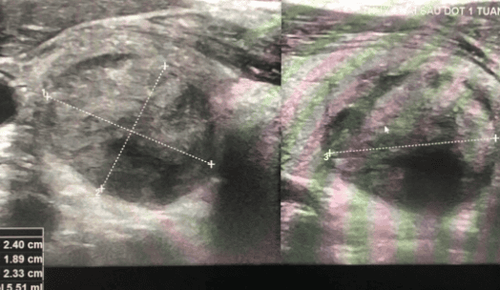

Chỉ từ tuần đầu tiên, tổn thương u giáp sau đốt đã cho thấy sự suy giảm đáng kể về kích thước và thường dự kiến giảm khoảng 50% thể tích trong tháng đầu và 90-95% trong 6 tháng, còn lại mô sẹo sau 12 tháng. Hình ảnh u đốt tốt sau điều trị không còn mạch máu trung tâm.